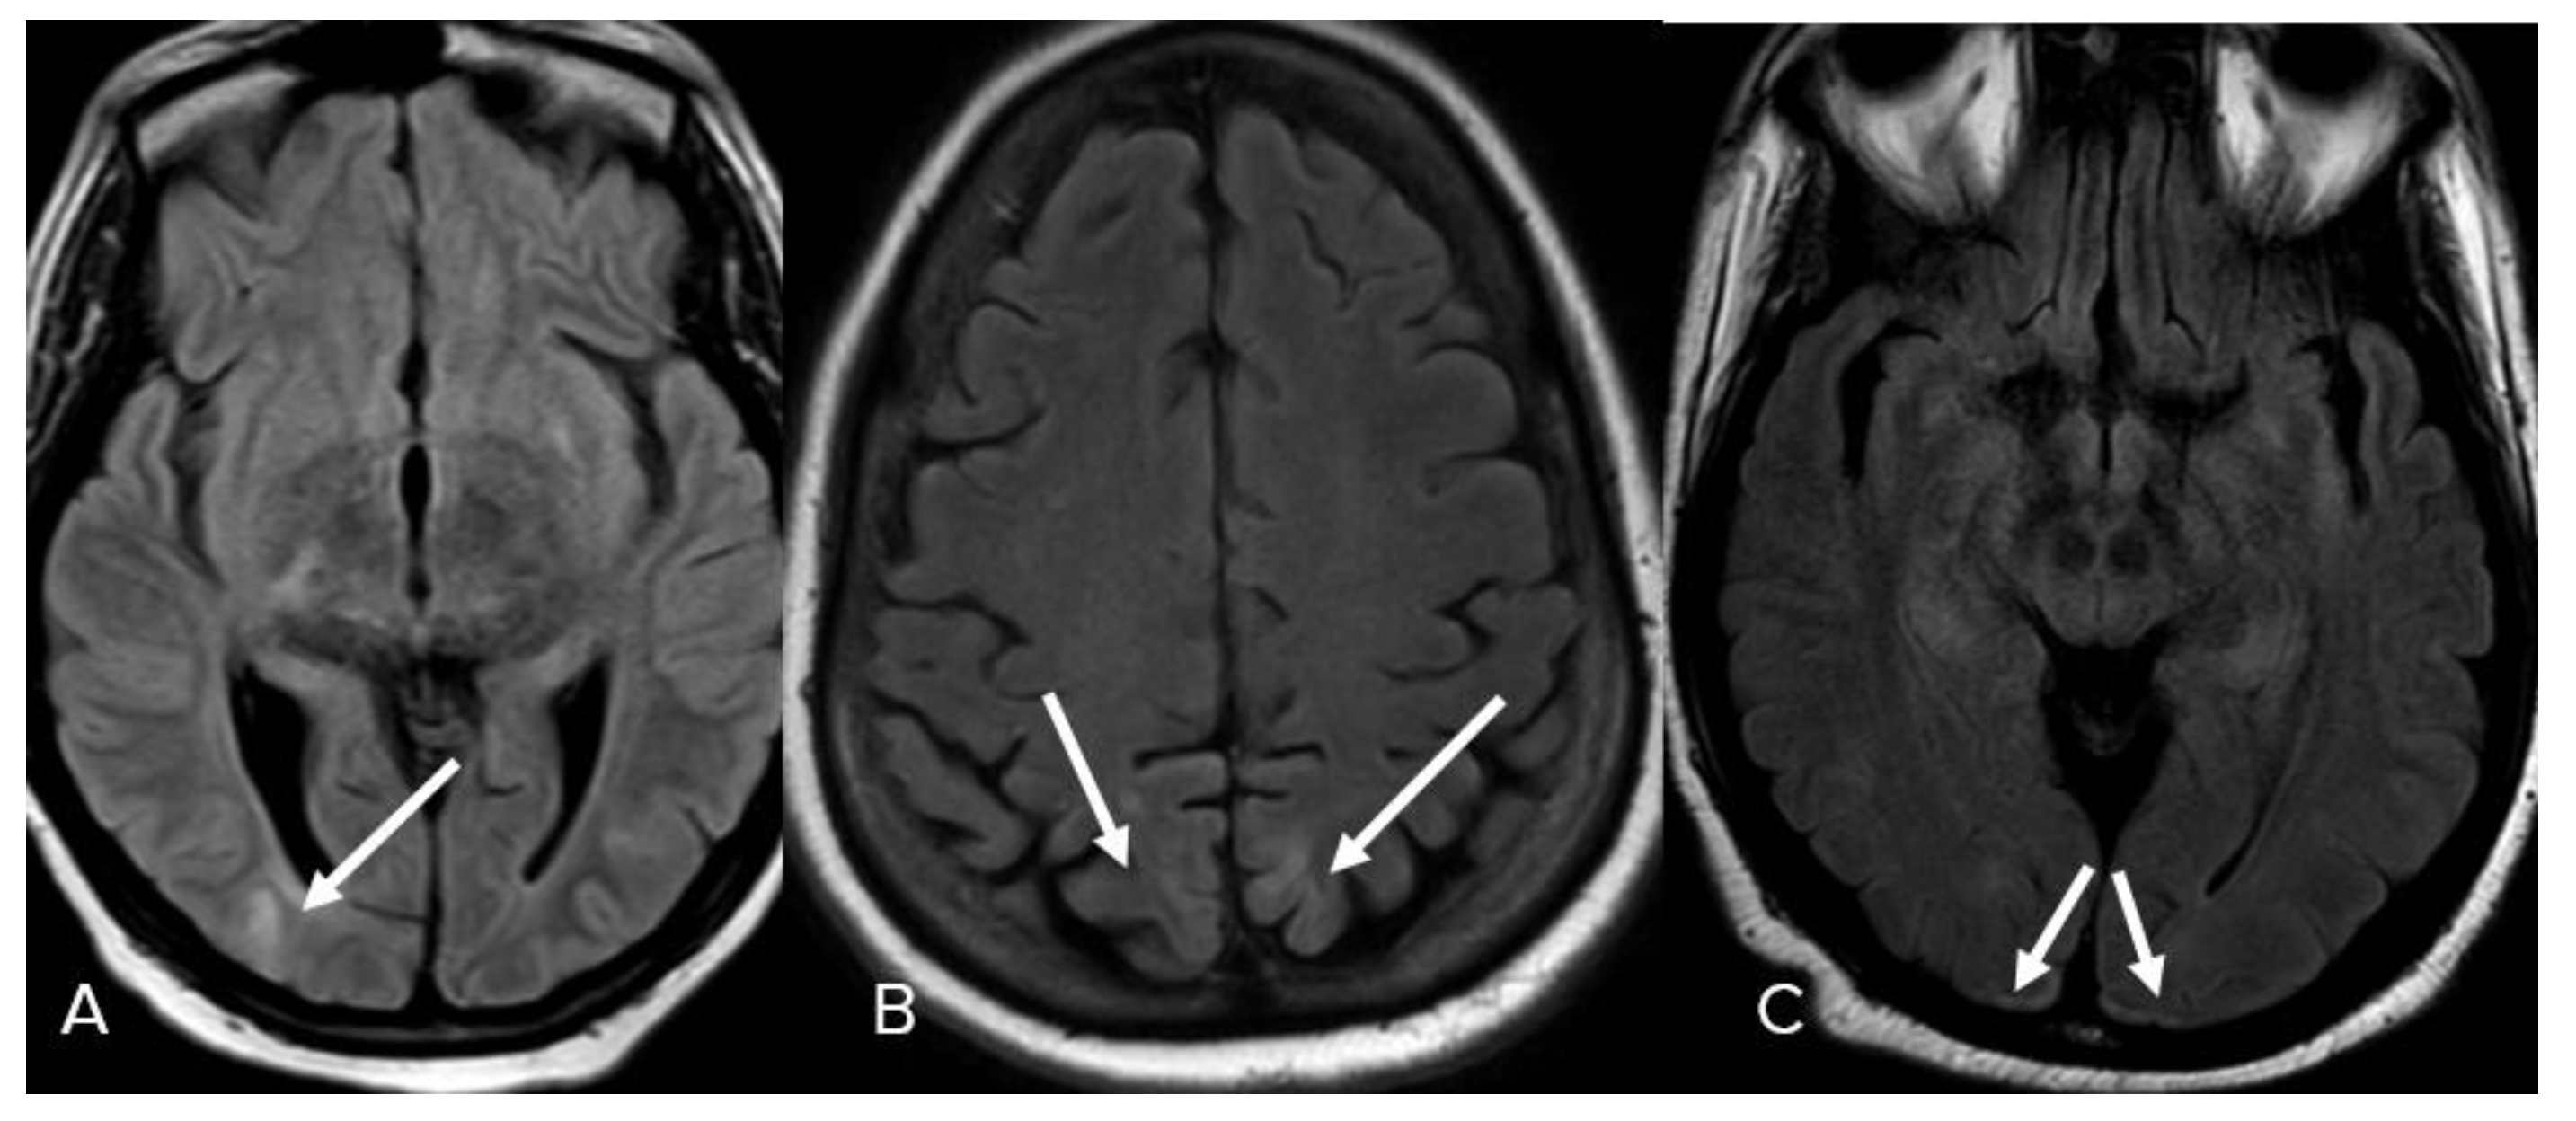

- Bulakbasi, N.; Kocaoglu, M. Central nervous system infections of herpesvirus family. Neuroimaging Clin. N. Am. 2008, 18, 53. [Google Scholar] [CrossRef] [PubMed]

- Oyanguren, B.; Sánchez, V.; González, F.J.; De Felipe, A.; Esteban, L.; López-Sendón, J.L.; Garcia-Barragán, N.; Millán, J.M.-S.; Masjuán, J.; Corral, I. Limbic encephalitis: A clinical-radiological comparison between herpetic and autoimmune etiologies. Eur. J. Neurol. 2013, 20, 1566–1570. [Google Scholar] [CrossRef] [PubMed]